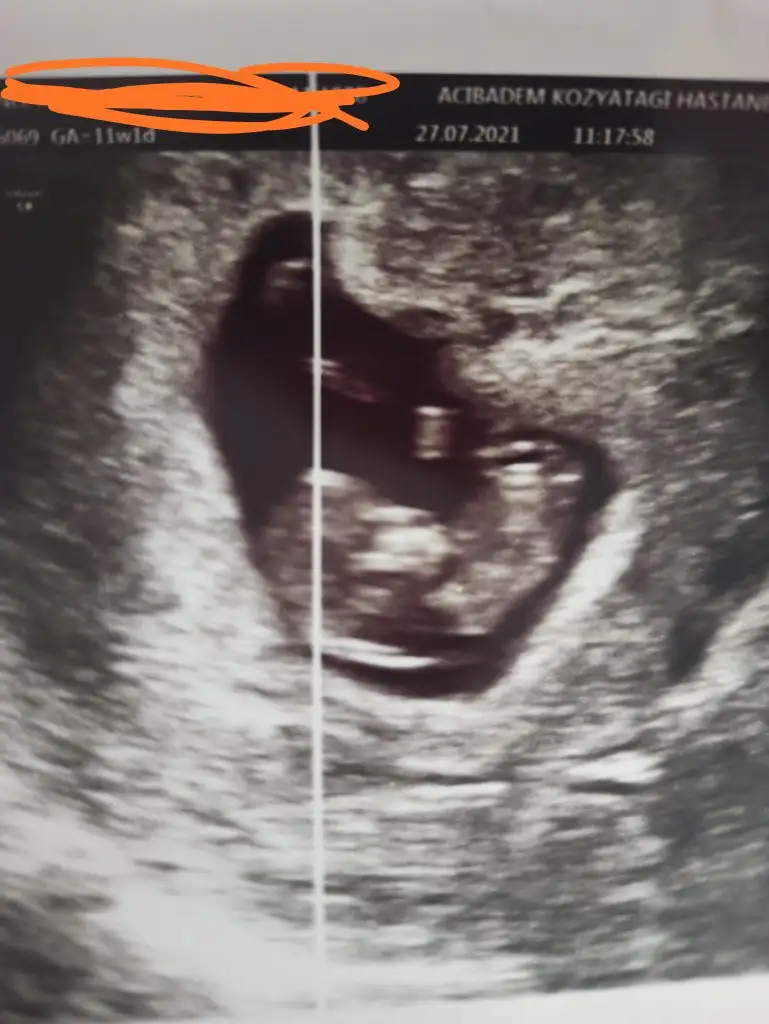

Doktor simdilik kiz diyelim dedi ama bakalm sabaha randevumuz var gozukurse yazicam insallah saglikla gelsin de hic farketmez sagolasin cevabin icin bide son ultrasonu atayim ona da bakiverErkek gibi

Doktor simdilik kiz diyelim dedi ama bakalm sabaha randevumuz var gozukurse yazicam insallah saglikla gelsin de hic farketmez sagolasin cevabin icin bide son ultrasonu atayim ona da bakiver![]()

Evet burada bacak arası boş görünüyor sağlıkla gelsin prenses

Erkek görünüyorEki Görüntüle 2893317 12+4 haftalık cinsiyet tahmini alabilir miyim ?

12+6 haftalık hamileyim cinsiyet tahmininiz nedir ?Erkek görünüyor![]()